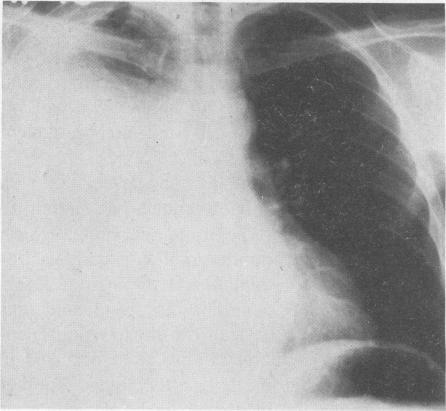

Unilateral hydrothorax secondary to ascites demonstration by a noninvasive radionuclide imaging technique.

West J Med. 1981 Mar;134(3):220-2.

Unilateral hydrothorax secondary to ascites demonstration by a noninvasive radionuclide imaging technique.通过无创放射性核素成像技术证实的腹水继发单侧胸腔积液。